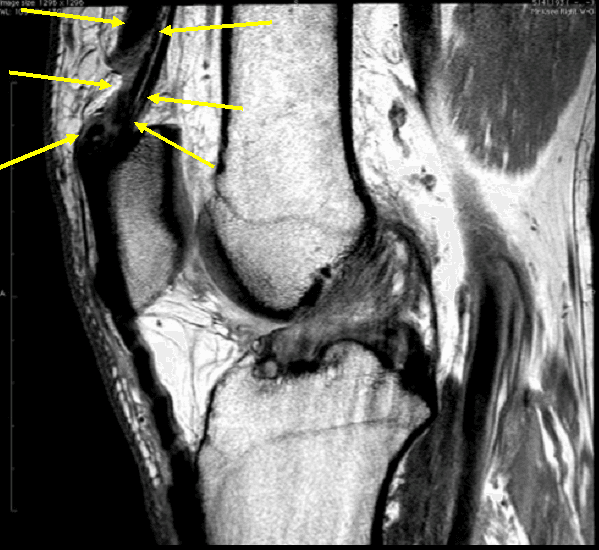

Sagittal MRI of the knee shows the positions of the five regions, which Quadriceps Tendonitis Mri We examined this layered configuration on mr images to determine if it is relevant in the evaluation of the traumatized quadriceps tendon. Diagnosis is made clinically with. While this part of the examination can be painful, it is important to identify a quadriceps tendon tear. To confirm the diagnosis, your. For example, computed tomography (ct) or magnetic resonance imaging (mri). Quadriceps Tendonitis Mri.

MRI scans of the right knee show a partial tear of the quadriceps Quadriceps Tendonitis Mri Diagnosis is made clinically with. We examined this layered configuration on mr images to determine if it is relevant in the evaluation of the traumatized quadriceps tendon. While this part of the examination can be painful, it is important to identify a quadriceps tendon tear. To confirm the diagnosis, your. The quadriceps tendon is a multilayered and laminated structure, as. Quadriceps Tendonitis Mri.